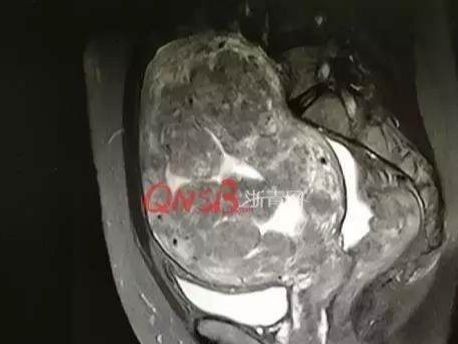

女子的影像学资料,肚子里满满的都是肌瘤

报道是这样描述的:数百颗瘤子将子宫撑大5倍,数不清的子宫肌瘤将子宫占满,还像鹅卵石一样紧挨着子宫内壁,并将血管紧紧包裹;手术中,稍有不慎割破血管就有可能导致患者大出血,小心翼翼地将动脉阻挡,再将子宫肌瘤一颗颗剥下来,1颗、2颗、3颗……整整110多颗,现场的医护人员惊呆了!